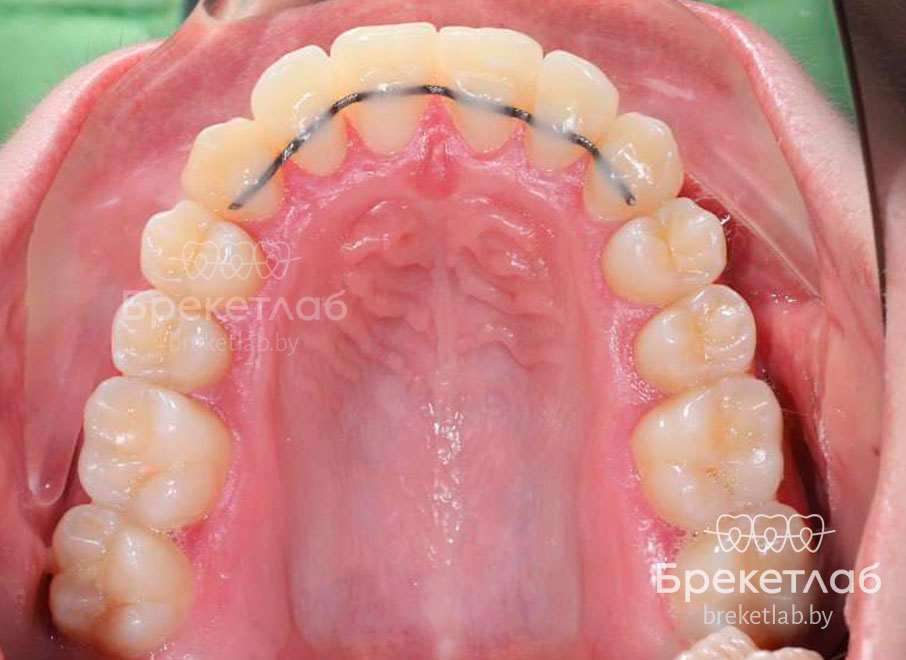

После снятия брекетов для закрепления результата установлены несъемные ретейнеры.